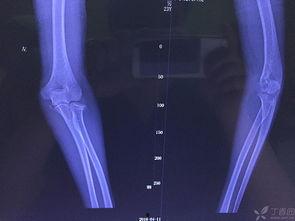

首先,得先了解一下什么是骨折塑形。简单来说,就是通过一系列的物理治疗和康复训练,让骨折后的骨头恢复到最佳状态。听起来是不是有点像魔法?其实,这背后可是有科学依据的。

这个视频里的主角,就是一位专业的物理治疗师。他手把手地教我们如何进行骨折塑形。从视频里可以看到,治疗师首先会评估患者的骨折情况,然后制定个性化的康复计划。

接下来,我们就来揭秘这个神奇的塑形过程。首先,治疗师会教患者进行关节活动度训练,帮助关节恢复灵活性。这个过程就像是在给关节做“拉伸运动”,让它们重新找回活力。